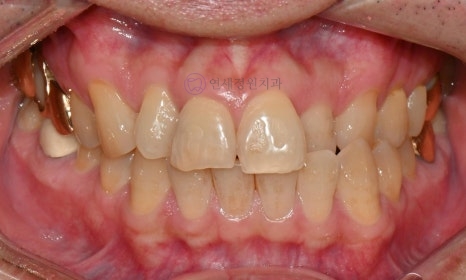

Evaluation of Tooth Color

When you visit the dental clinic for teeth whitening, a comprehensive oral examination and full scaling will be conducted first. If you have cavities or chipped teeth, or if there is inflammation around the teeth, treatment for cavities and gum issues must be performed before proceeding with whitening.

If there is cervical wear or if there are existing resin fillings in the teeth, there may be differences in tooth color after whitening, so caution is advised.

Before starting the teeth whitening process, the color of your teeth will be assessed. A shade guide will be used to record the tooth color; the shade guide is a specific indicator that expresses the degree of lightness or darkness of the teeth in stages. As the letters increase numerically, the color becomes darker. Tooth colors are classified into 16 stages, ranging from B1 to C4 (B1-A1-B2-D2-A2-C1-C2-D4-A3-D3-B3-A3.5-B4-C3-A4-C4). The closer to B1, the brighter the natural tooth color, and the closer to C4, the darker the color.

Shade Guide

A and B are generally closer to average tooth colors and are frequently used clinically, while C represents a darker shade with gray undertones. D is more common among Caucasians and relatively less common among Asians.

A: Orange (Brownish tones)

B: Yellow Orange (Yellowish tones)

C: Blue Orange, Greyish Orange (Grayish tones)

D: Reddish Grey, Pink Orange (Reddish tones)

Before and After

Before Shade: A3.5 / After Shade: A2

Before Shade: A2 / After Shade: B1